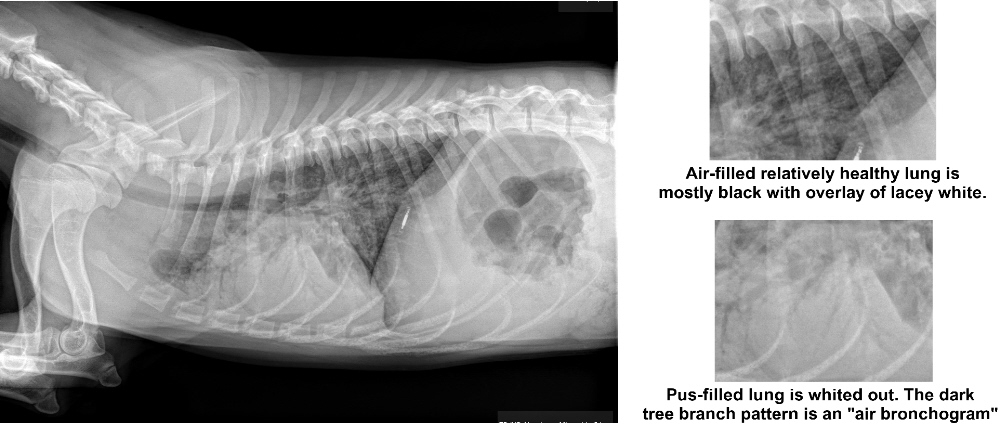

Рентгенодиагностика бронхопневмонии: Советы и примеры

Раздел: Альбом открытий